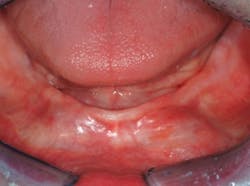

• (Figs. 2 and 3) Placement of two conventional-diameter implants, one each in the canine areas (implant diameter greater than 3 mm), an attachment on the implants, and an overdenture.

• (Figs. 4-6) Placement of at least four, one piece, small-diameter implants (SDIs) with spherical abutments, two implants at or near each of the canine areas or spread evenly from the canine-to-canine areas if bone presence permits (implant diameter less than or equal to 2.9 mm), and an overdenture.